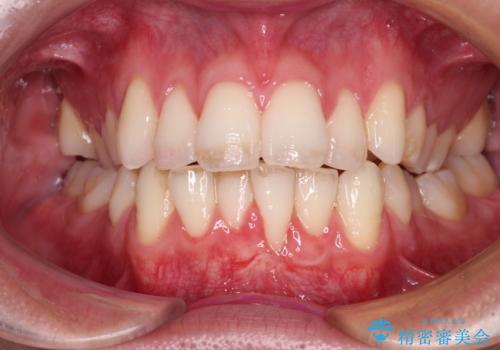

- 徐々に歯根が見えるようになり、気がついたら歯根のほぼ全てが見えるようなってしまったと言うことで来院された患者様です。

しみる症状はないものの、見た目が著しく悪く、汚れが溜まりやすいとのことで、歯肉移植による根面被覆を行うこととしました。